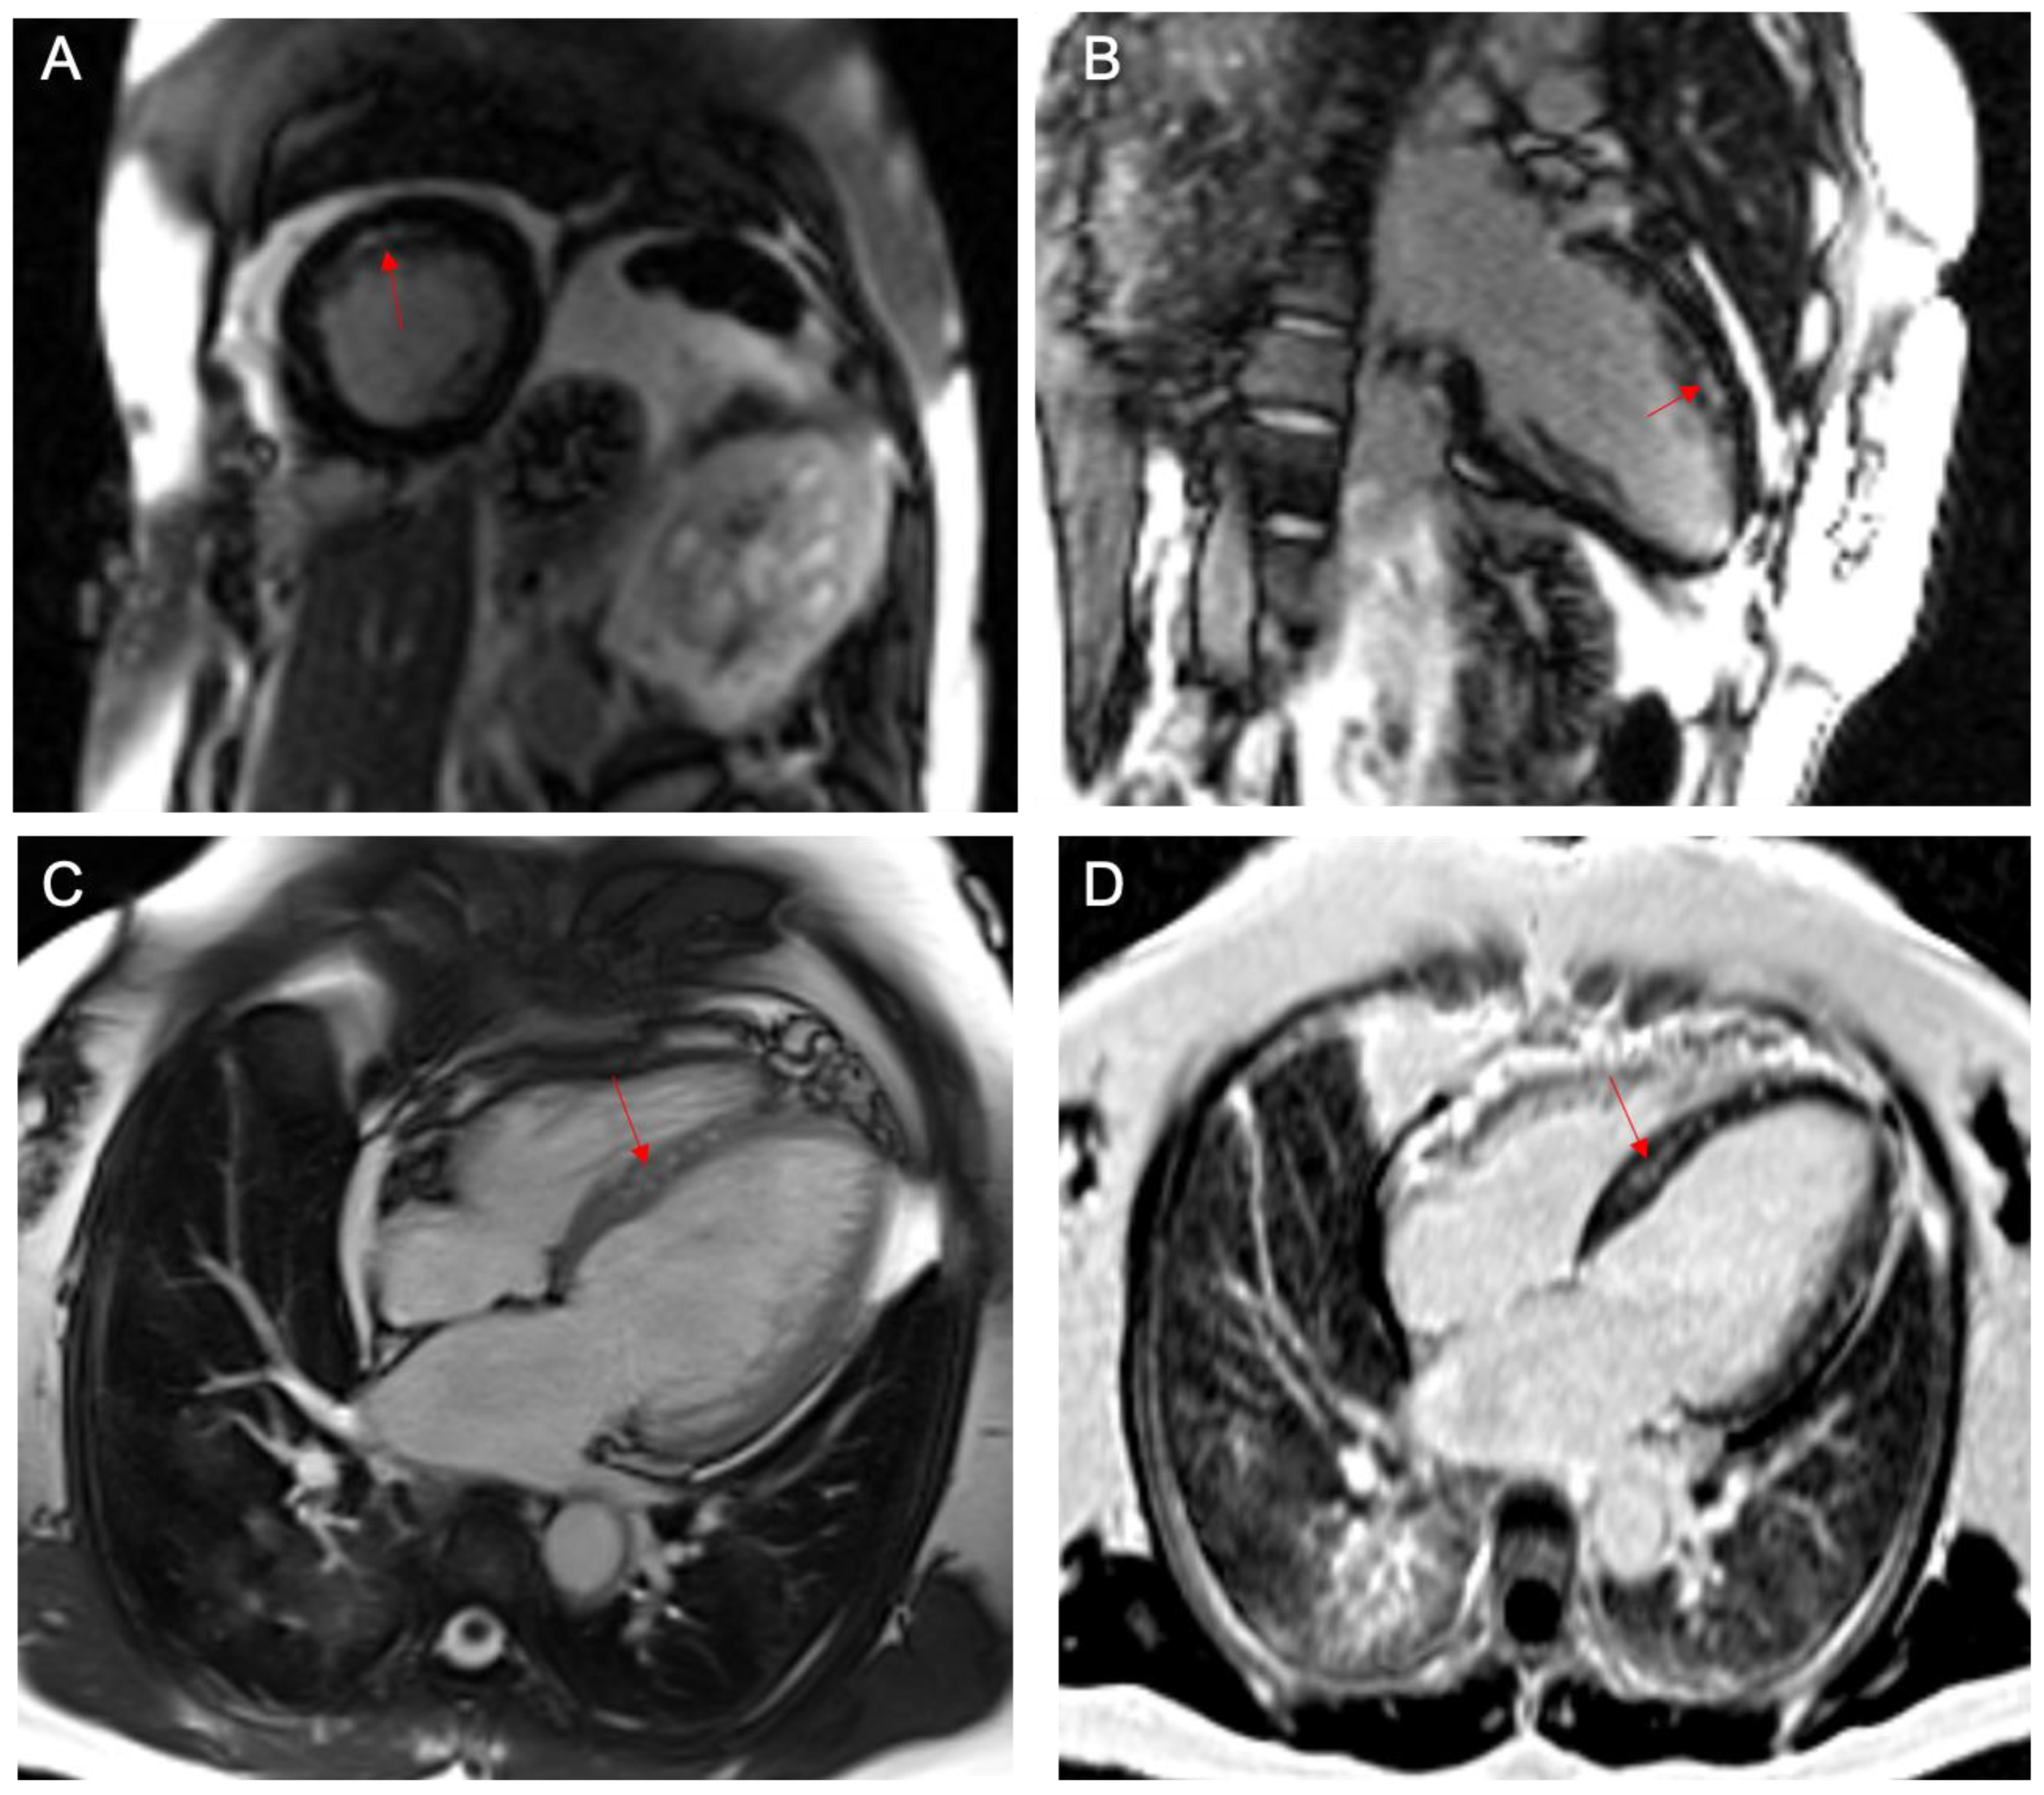

2. Case Report

Case Presentation